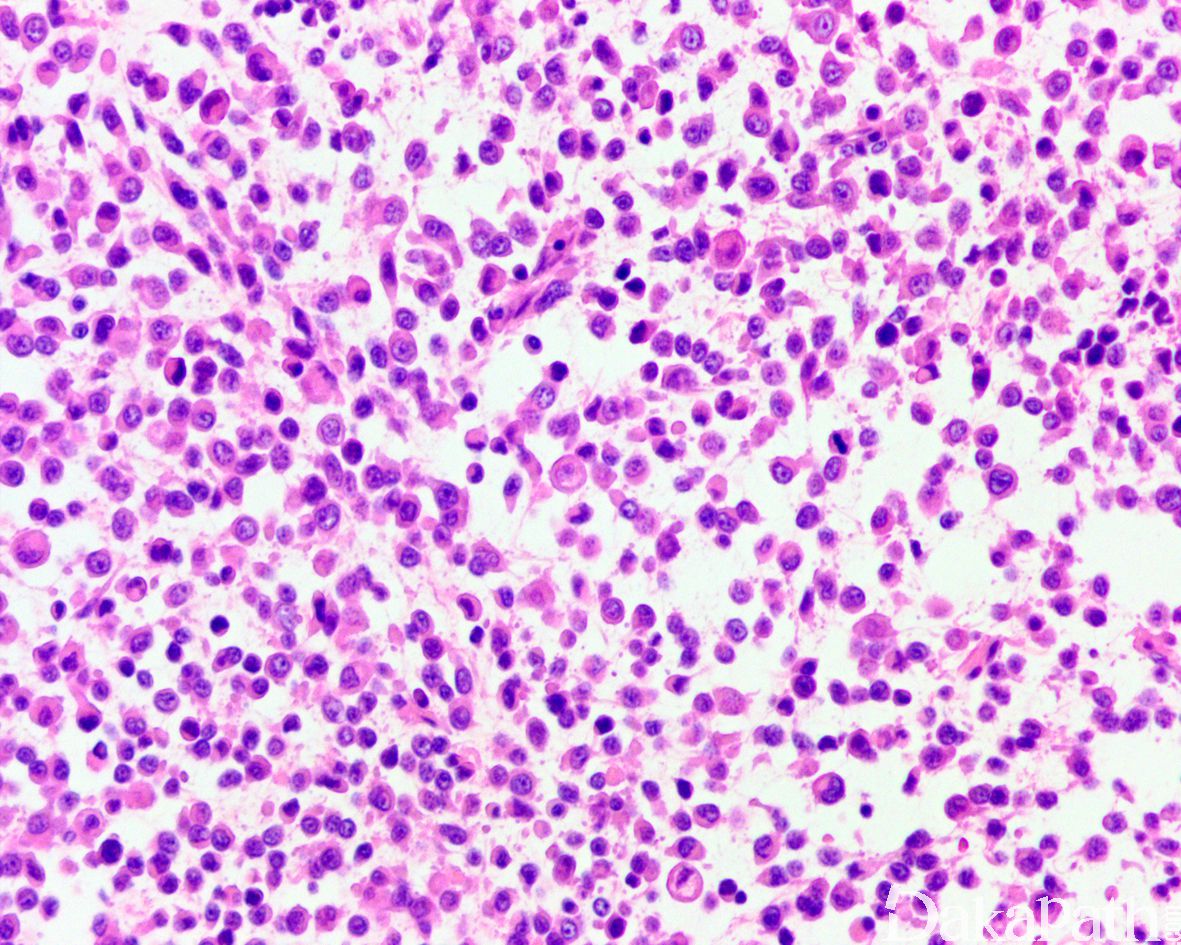

组织学表现为在疏松或黏液样间质中出现弥漫性排列的单个肿瘤细胞;

肿瘤细胞胞质透亮或嗜酸性,核大、中位或偏位,具有小核仁,似浆细胞或淋巴细胞,多形性不明显;

少数病例肿瘤细胞似印戒细胞,但与细胞外黏液无关,也称为印戒细胞样尿路上皮癌; 5.50%病例可找到高级别的普通型浸润性尿路上皮癌成分;